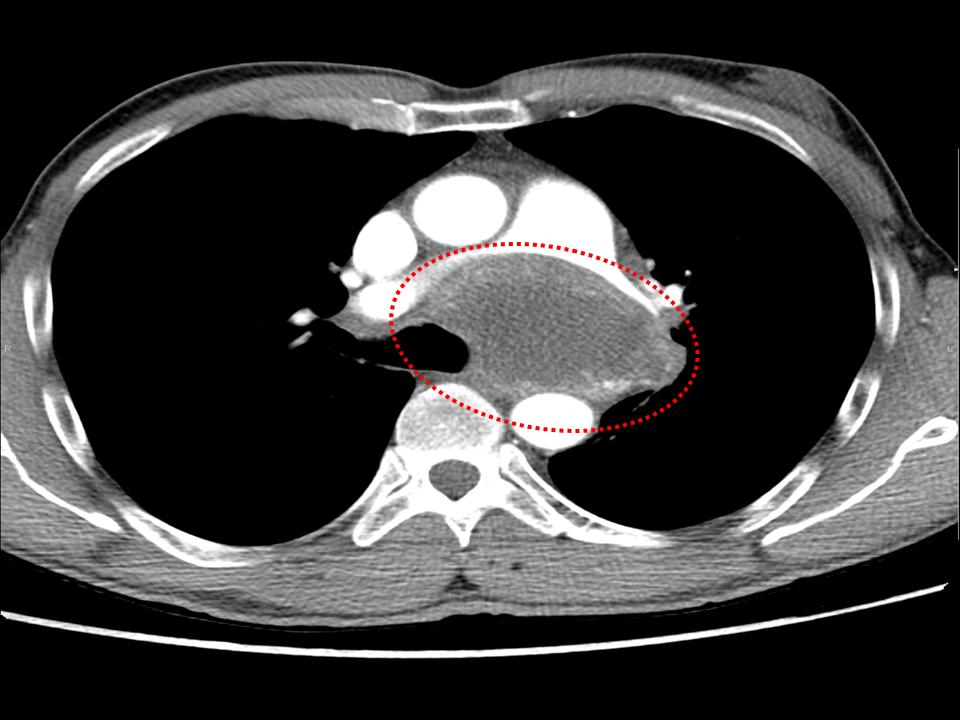

Dr. Ignacio Guasch, Dr. Edwin Mejía.

Hospital Germans Trias i Pujol, Badalona.

Hombre de 59 años, bronquítico crónico que refiere aumento del volumen mamario bilateral. Con una TC que informa masa tumoral en mediastino medio, voluminosa, sólido- quística, con extensa necrosis tumoral y adenopatías mediastínicas paratraqueales de tamaño significativo. Se realizar una PAAF guiada Ultrasonografía Ecobroncoscópica (EBUS) para el diagnóstico definitivo.